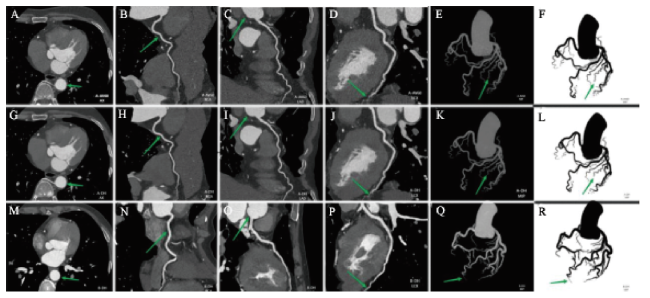

由2名具有4年工作经验的医学影像技师采用轮流监督的方法确保客观图像勾画准确,勾画原则:放大后轴面勾画、避开血管壁,取3次的平均,见图1。出现分歧时由具有17年工作经验的医学影像副主任技师实施最终勾画方案,读取数据。将ROI分别置于主动脉根(aortic root,AR)、左前降支(left anterior descending coronary artery,LAD)、左回旋支(left circumflex coronary artery,LCX)、右冠状动脉(right coronary artery,RCA)及同层胸前脂肪密度较均匀的区域内,记录各ROI的CT值及噪声值。参照测量层上下滚动测量3次,取3次平均值作为最终结果,计算各血管的信噪比(signal-to-noise ratio,SNR)和对比噪声比(contrast-to-noise ratio,CNR)。

图1 CCTA勾画示意图

注:A为A-AV60;B为A-DLIR;C为B-DLIR;红色为ROI测量RCA、LAD、LCX和胸前脂肪,黄色为勾画观察算法间噪声差异。

Figure 1 Schematic diagram of CCTA delineation

图2 A-AV60、A-DLIR、B-DLIR 3种方案CCTA的原始轴位、CPR、MIP图

注:从左至右为原始轴位和RCA、LAC、LCX、MIP、MIP反转图。A~L是50岁男性患者的检查图,A~F采用A-AV60,G~L采用A-DLIR,包括冻结后的原始轴位、CPR和MIP。M~R是54岁女性患者的检查图,采用B-DLIR,包括冻结后的原始轴位、CPR和MIP。A、C、G、I、M、O箭头所指反馈了主动脉及主动脉根部管腔内噪点的评级,A、C噪声明显;B、H、N箭头所指反馈了冠状动脉的锐利度,B模糊、与脂肪边界欠清晰、锐利度评分最低;D、J、P箭头所指反馈了冠状动脉末端纹理伪影,D血管末端呈现塑料感、结节样伪影,连续性差;E、F、K、L、Q、R箭头所指反馈了末端纹理和小分支的可见度,E、F末端纹理伪影明显、小分支显示度最差。综合以上因素,5分评分法显示B-DLIR、A-DLIR评分高于A-AV60。

Figure 2 Original axial、CPR and MIP images of CCTA with three schemes: A-AV60, A-DLIR and B-DLIR